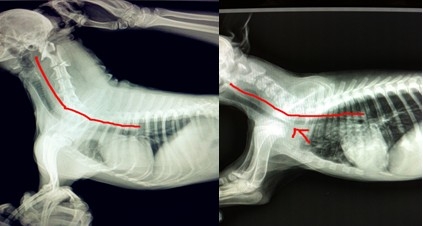

上面這兩張圖片來自于我院的兩張X光數(shù)碼片,第一張圖片是一根正常的氣管,第二張可以在尖頭所指的地方看見明顯的狹窄,由于此圖是手機翻拍,若為原圖,更加明顯,通過對比您可以清晰的發(fā)現(xiàn)區(qū)別和問題,所以及時就醫(yī)是非常積極的措施。